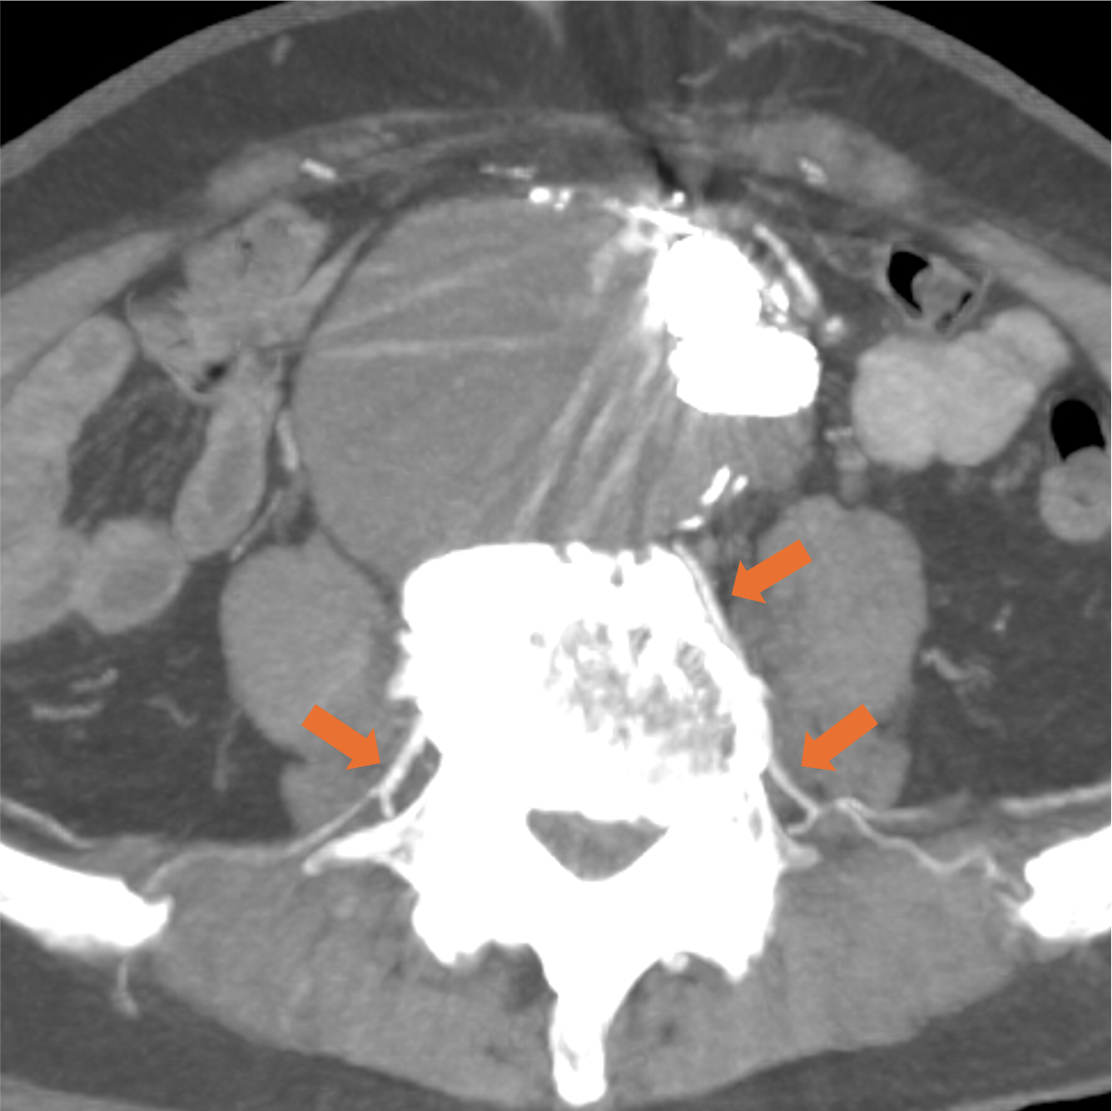

腹部大動脈瘤におけるTypeⅡエンドリークの診断と責任血管の検出

症例は80代男性。7年前に腹部大動脈瘤と右総腸骨動脈瘤に対しEVAR、2年前に腹部大動脈瘤のエンドリークに対し、下腸間膜動脈からコイル塞栓を行っている。動脈瘤が拡大傾向であったため、超音波検査が行われ、エンドリークが疑われた。評価と治療方針決定が必要と判断されたが、腎機能障害があったため入院での造影CTが計画された。

大動脈瘤は様々な要因で生じ、破裂により80-90%と非常に高い致死率を引き起こす疾患である。治療にはしばしば大動脈ステントグラフト内挿術(EVAR)が選択され、破裂のリスクを大きく減少させることが可能である。一方、ときにEVAR後も瘤が増大し、破裂する場合があるため、治療後の経過観察が必要である。増大が継続する場合、その原因としては瘤内への血流の残存(エンドリーク)があることが多い。エンドリークはその原因によって4つのタイプに分類され、それぞれ治療法が異なる。そのため、多くの施設において、エンドリークが疑われた症例では造影CTが行われ、治療方針の検討に使用されている。本症例のように分枝血管からの逆流はTypeⅡに分類され、その治療にはコイルや液体塞栓物質によるTAEや開腹手術が行われる。腹部大動脈瘤であれば上下腸間膜動脈や腰動脈、腸腰動脈等、様々な血管が流入血管となり得るが、本症例のように造影CTで予め流入血管とその経路を同定しておくことで、円滑な治療のアプローチを行うことが可能である。

CT技術や撮像プロトコル設定について

当院で使用されているCTは256列でのDual energy CTの撮影が可能なGEヘルスケア社のRevolution CTである。従来のSingle energy CTは1種類の管電圧を使用し、1種類のX線エネルギーを使用した撮像を行うが、本機種では高管電圧と低管電圧の2種類の異なる管電圧からそれぞれのX線エネルギーを使用した撮像が可能である。それにより、高画質かつ高コントラストの水密度画像とヨード密度画像が作成可能で、Deep learningを用いて解析を行うことでノイズの低減されたCT画像を再構成できる。本症例のようにTypeⅡエンドリークでは微小な血管が関与している場合があり、その検出と詳細な血管走行の確認において高コントラストかつ高画質の画像が求められ、Dual energy CTは有用である。